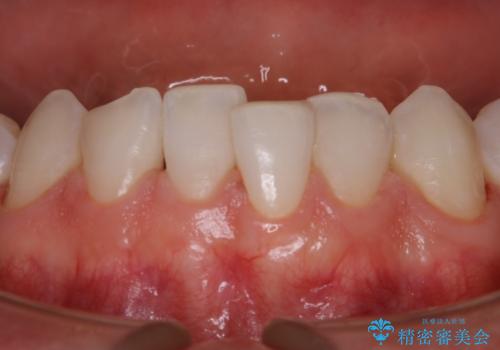

30代男性 虫歯の治療前にPMTC

- 歯医者でのクリーニングはかなり久しぶりで、今後虫歯の治療もしていくので綺麗にしたいとのことでした。PMTC30分コースを行いました。